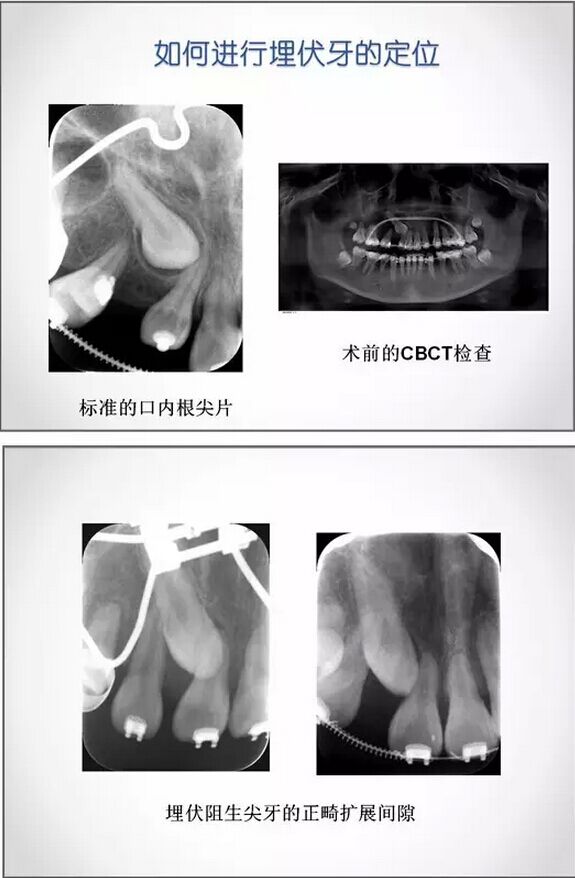

埋伏牙正畸治療中的外科開窗術(shù)

4.jpg